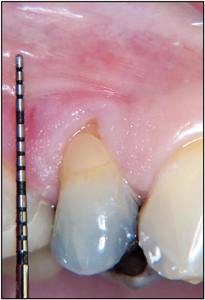

Gingival Augmentation: High Powered 970nm Diode Laser

Benjamin fig 1 alternate text for this image

Early analysis and diagnosis of soft tissue abnormalities and discrepancies enhances the clinician’s ability to attain the best possible outcomes with minimally invasive procedures. All too often, conditions are allowed to progress to their more advanced stages due to the erroneous thought process that the treatment is more disruptive than the pathologic condition itself. Today, … Read more